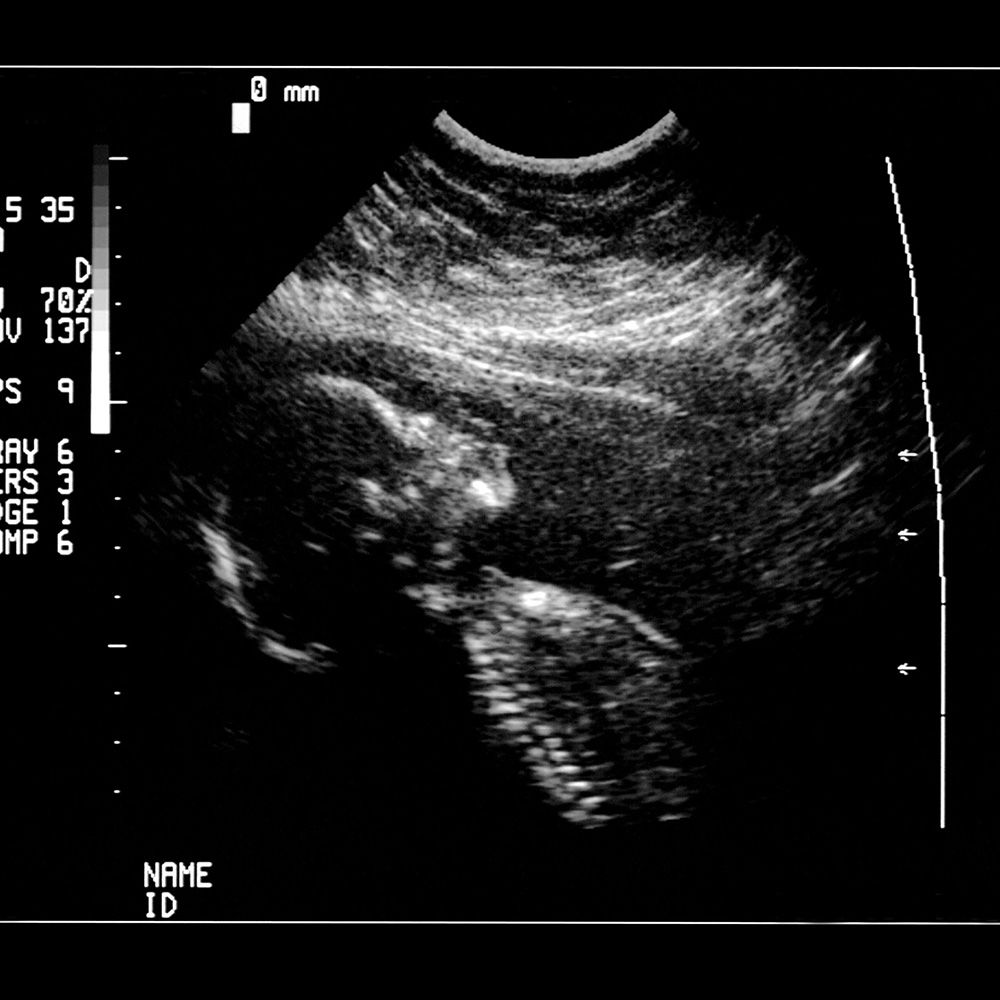

Узи это вредно

Узи это вредно 112 фото